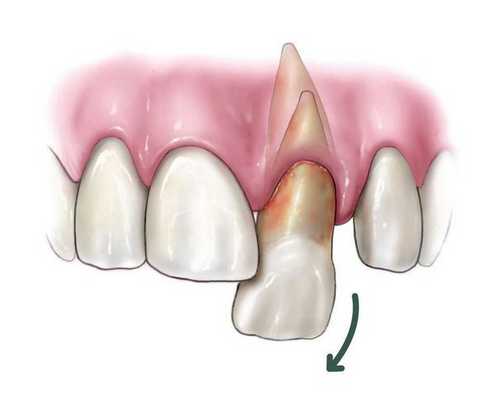

Вывих зуба — это патологическое перемещение зуба по отношению к альвеоле (костной лунке, в которой фиксируется зуб), вызванное насильственным механическим воздействием и сопровождающееся повреждением периодонта (связки, которая окружает зуб) и сосудисто-нервного пучка зуба (пульпы) [1] .

Неполный вывих характеризуется сохранением зуба в его лунке и сопровождается разрывом части волокнистых структур, окружающих и удерживающих зуб, либо растяжением волокон в той или иной степени. Для данной патологии характерно изменение положения коронки зуба и корня в зубном ряду по отношению к стенкам альвеолы. Зуб имеет неправильное положение вследствие смещения в вестибулярную ( в сторону губы) или оральную сторону, в сторону соседнего зуба или поворота вокруг оси. Это приводит к нарушению формы зубного ряда. Неполный вывих может сочетаться с переломом коронки, корня зуба или альвеолярного отростка.

Полный вывих характеризуется полным разрывом волокнистых структур периодонта (в том числе круговой связки зуба). При этом травмированный зуб в лунке отсутствует, а сосудисто-нервный пучок зуба всегда разрывается. Вывих может сопровождаться переломом края альвеолы. Иногда зуб может присутствовать в альвеоле за счёт единичных сохранившихся волокон круговой связки. По статистике полному вывиху чаще подвергаются фронтальные зубы верхней челюсти, реже — нижней. Меньше других подвержены полному вывиху клыки.

Вколоченный вывих — это травма считается наиболее неблагоприятной. Тело зуба под воздействием большой давящей силы погружается в ткани челюсти (он входит глубоко в лунку) и корень внедряется вглубь альвеолярного отростка и тела челюсти. Для вколоченного вывиха также характерен полный разрыв волокон периодонта. Крайне редко некоторая их часть сохраняет свою непрерывность, но существенно растягивается и надрывается. Сосудисто-нервный пучок, как правило, разрывается. Из-за внедрения более широкой части зуба в более узкую происходит деформация стенок альвеолы: они раздвигаются и ломаются. Данный вид вывиха иногда сопровождается поворотом зуба вокруг оси, смещением в вестибулярном или оральном направлении. Особенно это касается верхних зубов, когда вследствие вывиха может произойти повреждение носовых (гайморовых) пазух.

Согласно Международной классификации болезней 10 пересмотра (МКБ-10) код вывиха зуба — S03.2. Различают три вида [1] [3] :

- неполный вывих (при этом зуб частично остается в костной лунке);

- полный вывих (зуб полностью отсутствует в лунке);

- вколоченный вывих (зуб вколачивается в костную лунку).